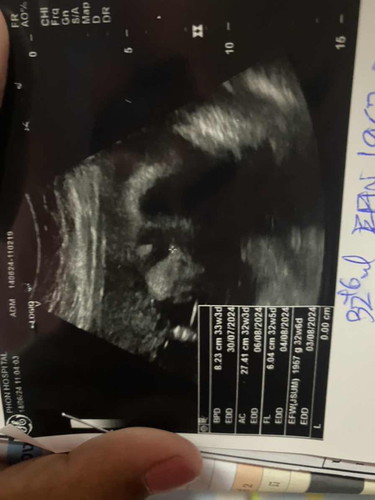

แบบนี้จมูกปากน้องปกติไหมค่ะ หรือเป็นเพราะฟิล์มภาพค่ะ แม่แอบกังวล